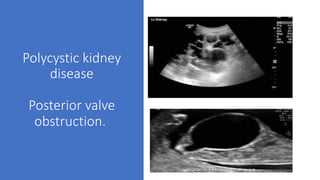

Polycystic kidney

disease

Posterior valve

obstruction.